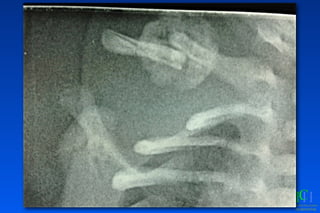

Fx Clavícula

Fx Clavicula: Criterios quirúrgicos

✓Fx abiertas

✓Hombro flotante

✓Pseudoartrosis

✓Interposicion de partes blandas

✓Compromiso neurovascular

✓Compromiso pleuropulmonar